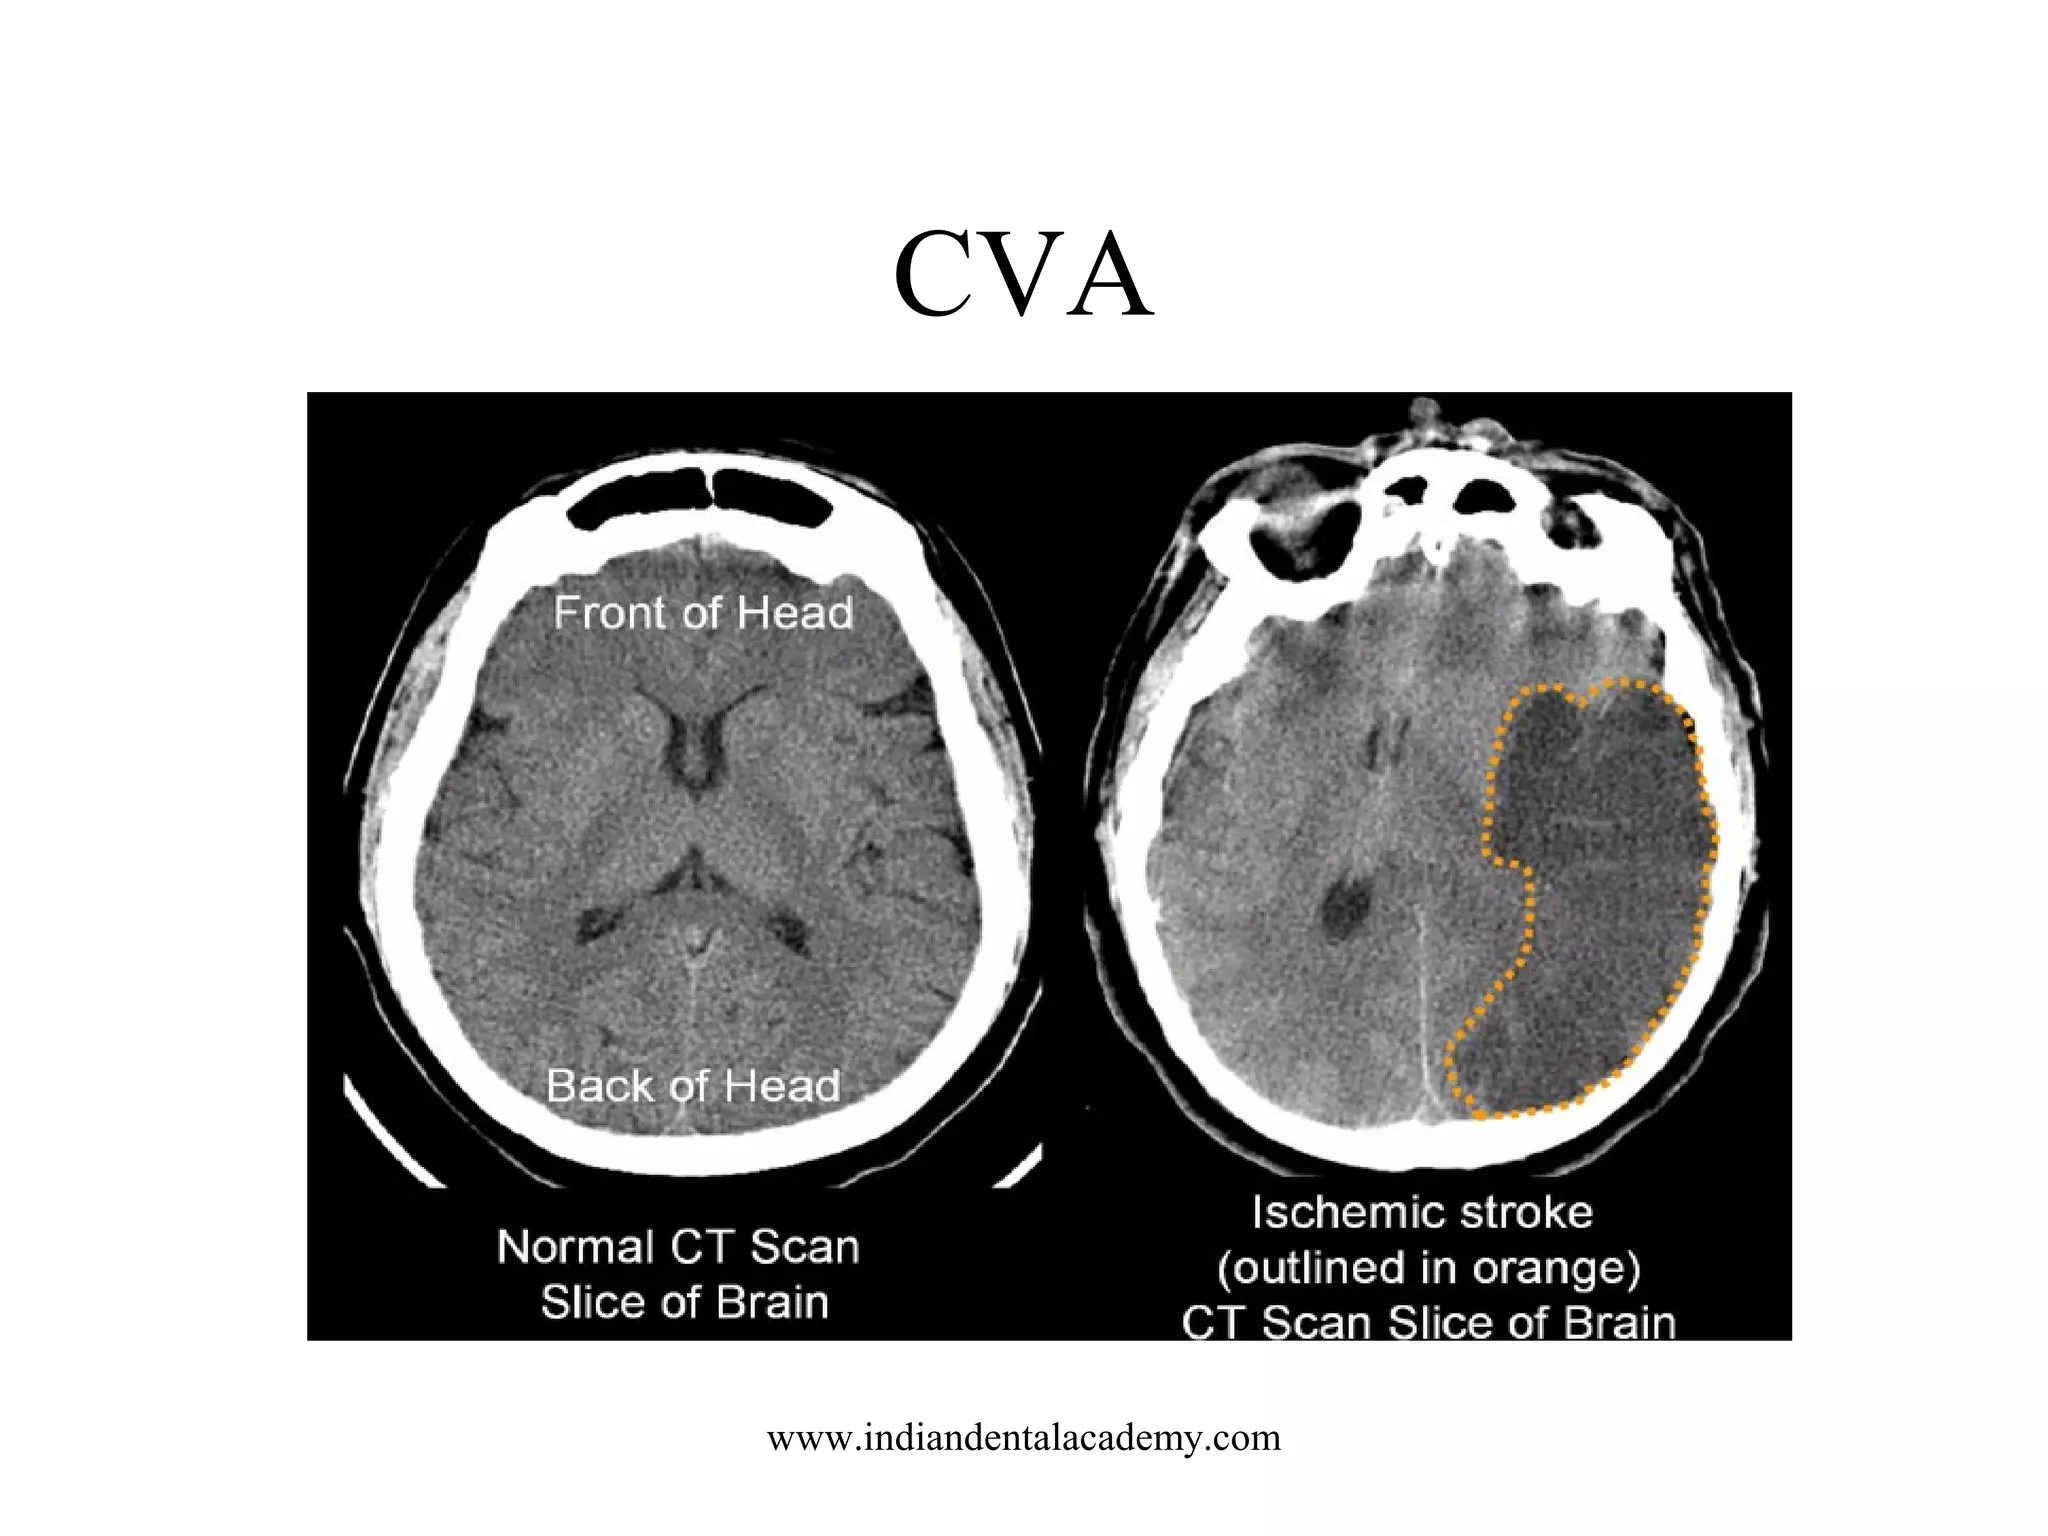

CVA

www.indiandentalacademy.com

This is a CAT scan of a patient with a bleeding stroke

caused by CAA. The two bright areas represent recent

areas of bleeding into the brain. Both areas are in the

outer part of the brain that is characteristic for CAAwww.indiandentalacademy.com

related strokes.